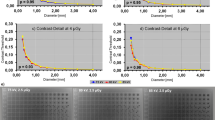

The mean dark-field contrast is depicted in Fig. 3. The contrast decreases towards higher energies. This is in accordance with the results from the reader study, where the dark-field signal strength score also decreases for higher energies. Even though contrast is highest for lower energies, the standard deviation (bars) for lower energies is higher than for higher energies. Looking at the mean contrast to noise ratio (CNR) in the lung one can see, that highest CNR is achieved at 60 to 70 kVp.

Left: Dark-field image of the Lungman, acquired with a tube voltage of 70 kVp. In the image position of the ROIs in the lung (a–f) and the position of the ROIs in the vicinity of the lung (g) are highlighted. Right: Mean contrast (top) and mean CNR (bottom) of the dark-field lung signal plotted for all examined tube voltages.

Quantitative evaluation of dark-field signal

Six regions of interest (ROIs), one in each lung zone, and one ROI in the vicinity of the lung (shoulder area) were selected for quantitative evaluation (Fig. 3). Each ROI has a size of \(30 \times 30\) pixels corresponding to \(12~ \times ~12\;{\text{mm}}^{2}\) in the patient/phantom plane. The size and position of the ROIs were selected such that ribs were excluded from the ROI and thus from the evaluation.

To reduce the influence of features from the cotton wool on the evaluation, a Laplacian Pyramid was used. Here, the images are separated into subbands, that contain the different frequency components of the image. The high frequency band (\({L}_{0}\)) contains uncorrelated noise and is therefore used for the noise characteristics of the dark-field images.

Mean values \({\mu }_{r,U}\) of the dark-field images and standard deviation \({\sigma }_{r,U}\) of the high frequency bands were calculated for each ROI \(r\) at every tube voltage \(U\) (for abbreviations also see Fig. 3):

Furthermore, the dark-field contrast \(C_{{r,U}}\) between an ROI in the lung and the ROI in the vicinity of the lung and their standard deviations \(\sigma _{{r,U}}^{{\left( C \right)}}\) were calculated using:

From these values the contrast to noise ratio \(CNR_{{r,U}}\) was calculated for each ROI in the lung: